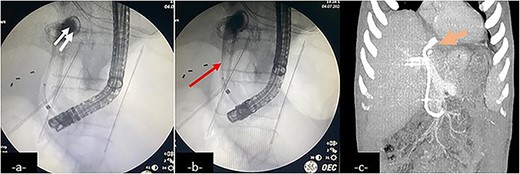

An endoscopic retrograde cholangiopancreatography (ERCP) showing contrast leakage from left-sided bile duct (a, double arrow) with duodenal fistula communicating with the biloma, drained by an inserted stent (b, arrow). Follow-up coronal CT-scan reconstruction after ERCP shows the internal drainage (c, large arrow).